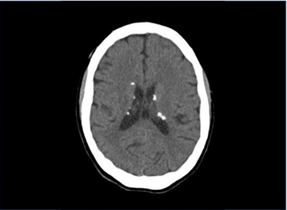

Menina, 4 anos, é trazida à consulta por crises convulsivas. Na avaliação, apresenta atraso de linguagem e, ao exame clínico, observam-se máculas hipopigmentadas em regiões lateral direita de abdome, perna direita, inguinal esquerda e dorso (fig.1). Observam-se nódulos eritematosos em região malar bilateralmente e dorso de nariz (fig.2). O exame de imagem apresenta nódulos subependimários (fig.3) e lesões em hiperdensas em parênquima cerebral. Apresentou síndrome de West no primeiro ano de vida.

enunciado 1517163-1enunciado 1517163-2enunciado 1517163-3

Figura 1 Figura 2 Figura 3

Com base nos dados apresentados, o diagnóstico do caso é: